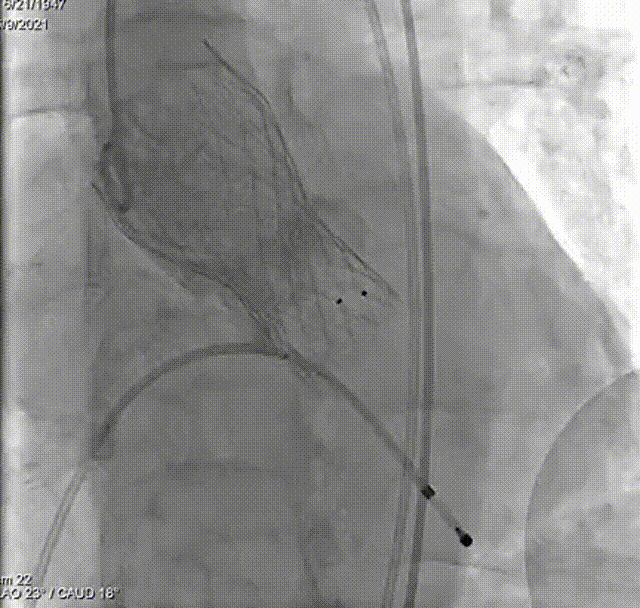

输送系统输送至窦底,行主动脉根部造影,借助无冠窦猪尾造影定位,由于该患者基础心率较缓慢,瓣膜无起搏顺利释放。

释放

术后心电监护未见传导阻滞。即刻造影和测压显示基本无压差和无反流。